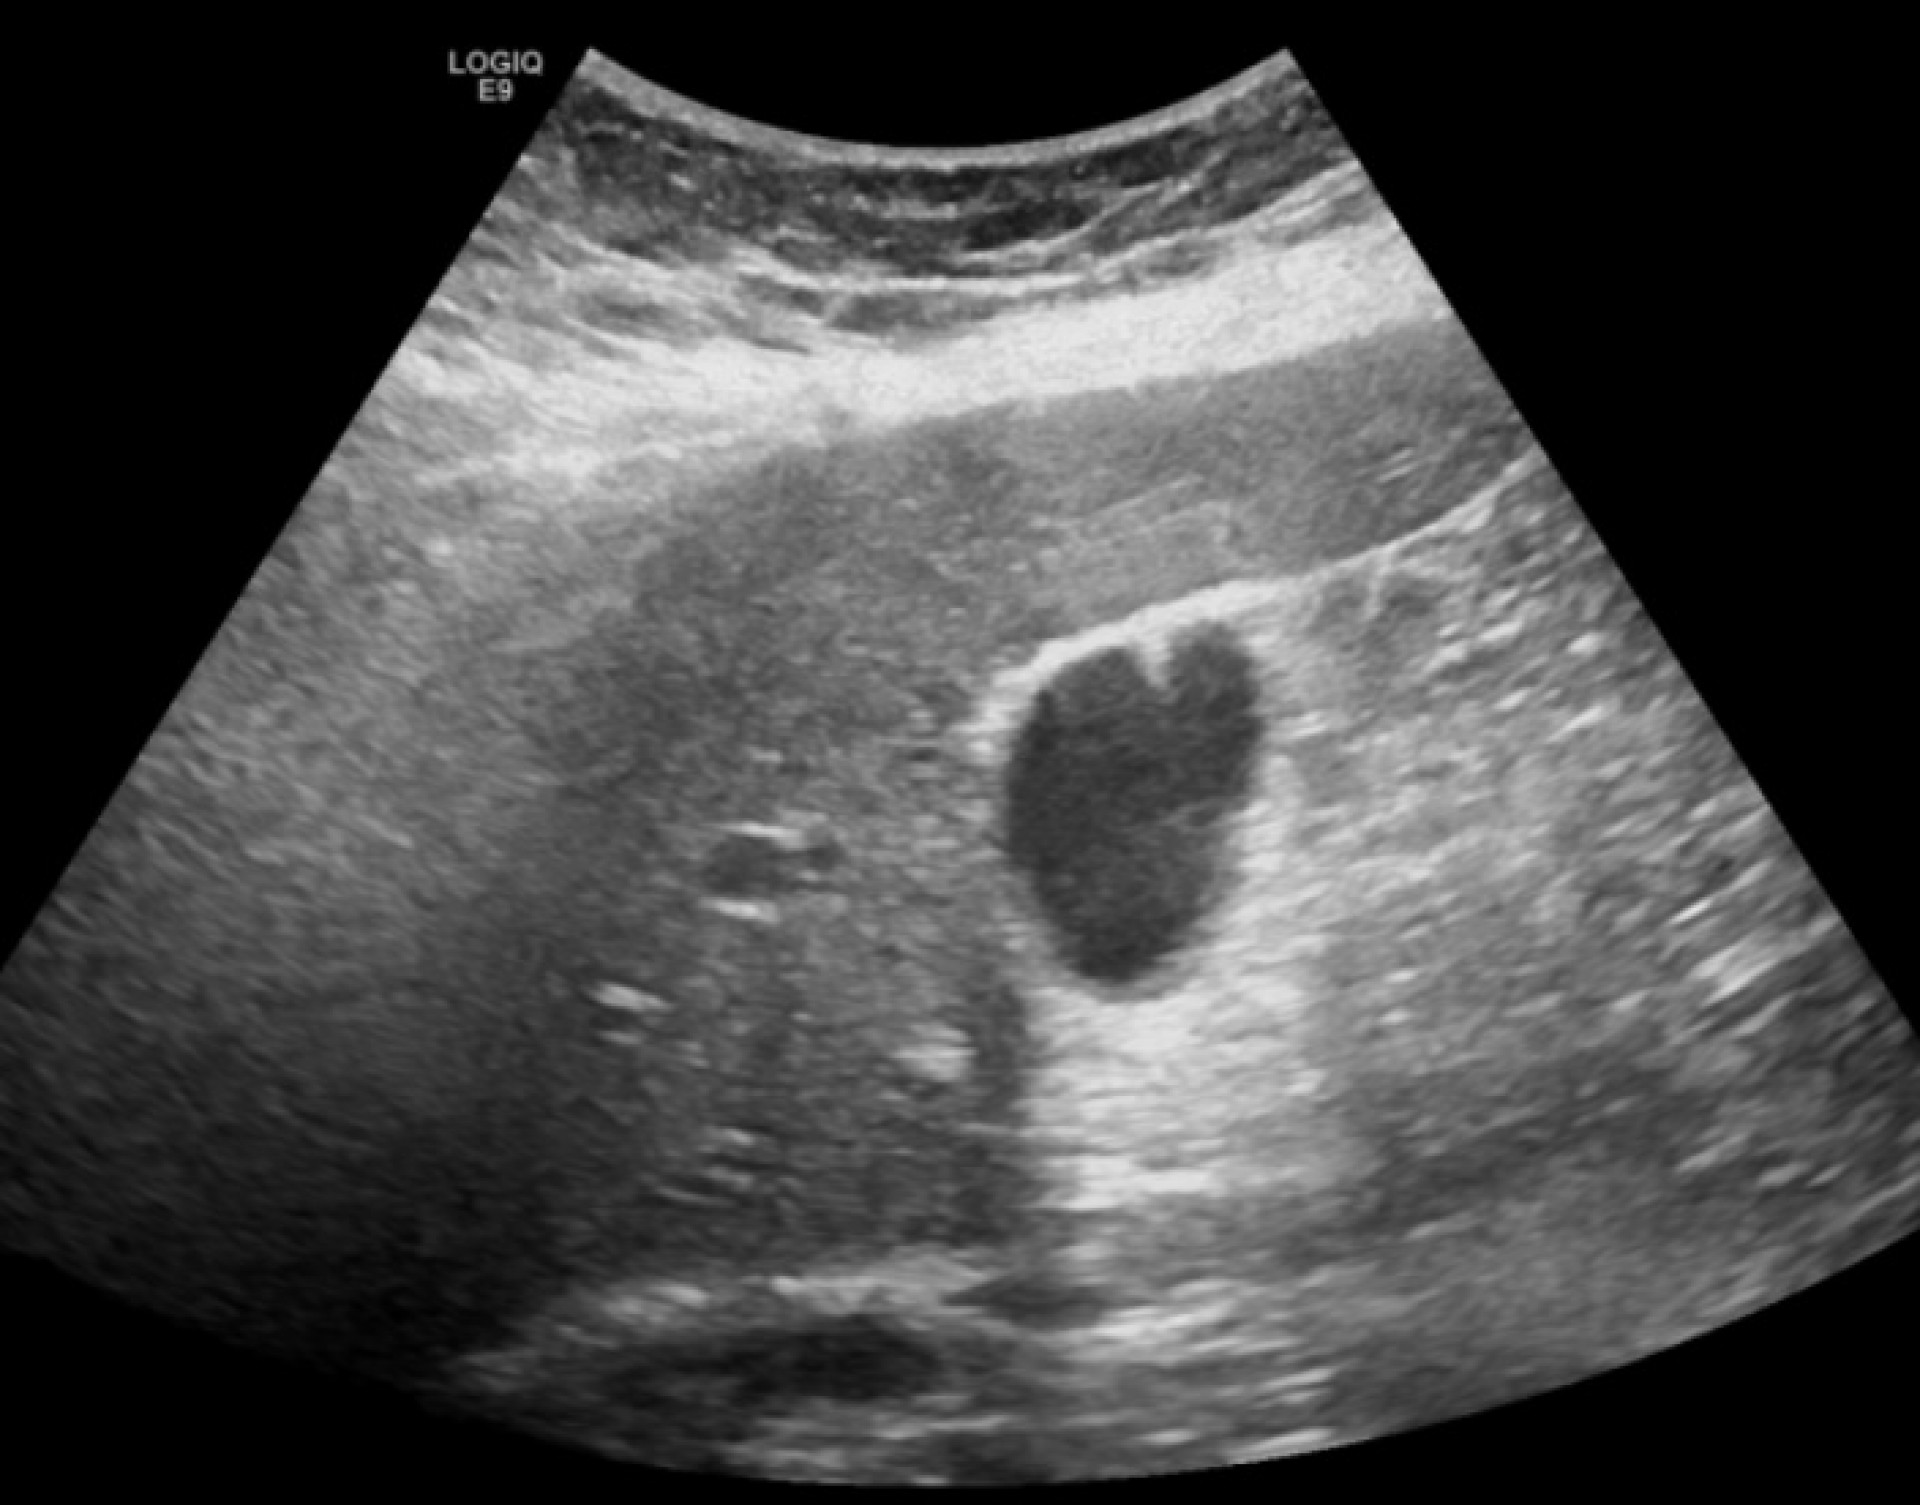

- Er zijn ook 2 specifieke subtypes van het reverberatie artefact: comet-tail artefact en ring-down artefact

- Ring-down artefact: Lijkt qua beeld op een comet-tail artefact, maar is nog denser (witte streep) doordat er nu continu een signaal wordt teruggekaatst. Dit gebeurt als je een tetrahedron van luchtbubbels hebt met in het midden een vochtpocket. De weerkaatsing in deze structuur is praktisch continu. Dit is dus een teken van de aanwezigheid van lucht, bijvoorbeeld in een abces, een vat (portoveneus gas) of de wand van een structuur (emfysemateuze cholecystitis)

Ring-down artefact; Afbeeldingen van European Society of Radiology - EPOS